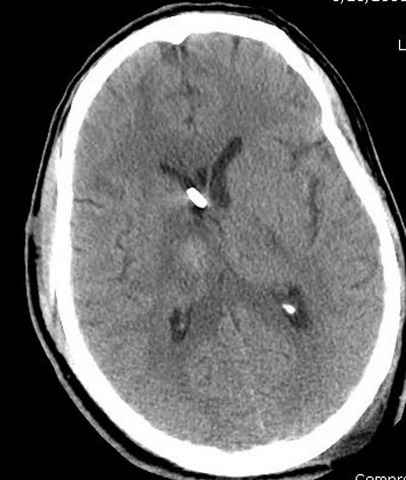

больному 42, автоавария, политравма, открытая черепномозговая травма, безсознании, открытый перелом бедра, размозжение мягких тканей, дефект кожи на передней поверхности бедра около 13 см2 от ожога, компартмент синдром.

Наблюдается службой травмы и нейрохирургии (ICP) Increased Intracranial Pressure by ventricular cateter

больной без сознания, со слов нейрохирурга, наблюдается положительная динамика в нейрохирургическом статусе.

монииторинг